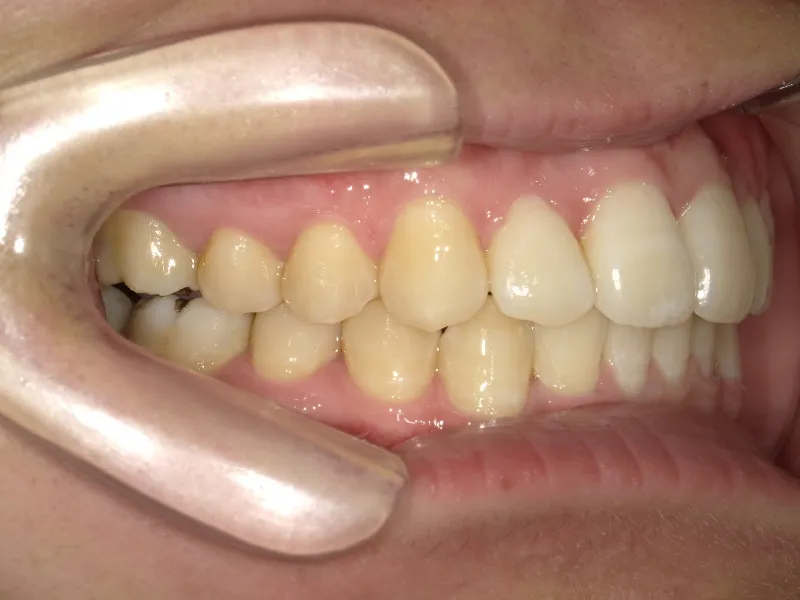

治療回数○回、2年9ヶ月の治療期間で矯正治療を終了しました。

主訴が改善され、ご満足頂きました。